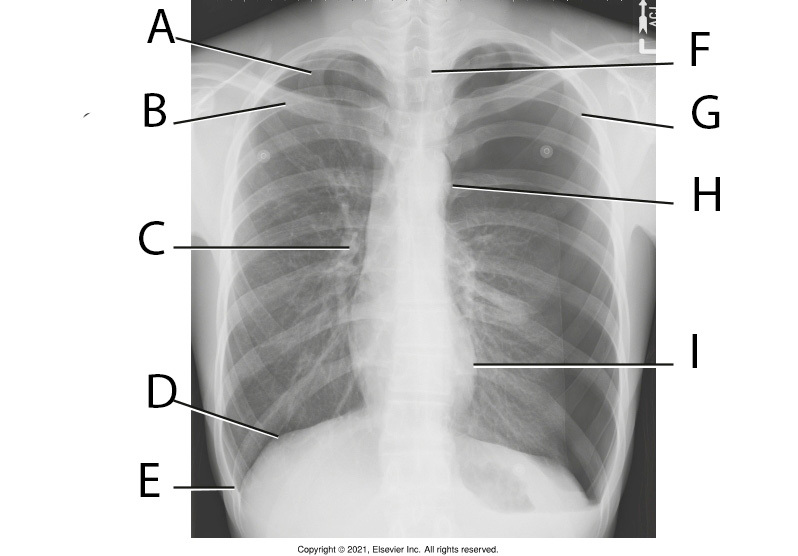

1

Q

A

Apex, apicie

2

B

Clavicle

3

C

Hilum

4

D

Right Hemidiaphragm

5

E

Right costophrenic angle

6

F

Air-filled Trachea

7

G

4th rib

8

H

Aortic arch

9

I

Heart